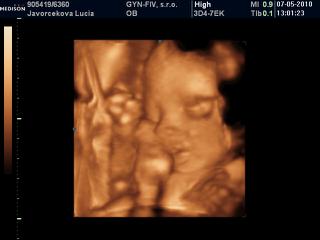

Lucy, nádherná je 😵

Bihan, dakujem 😵 ja som neobjektivna, pre mna je najkrajsia pod slnkom 😀

Lucy kraaaaaaaaaaaasna je 😵 😵 😵

A inak poloha je zadkom dole, hlavicka niekde v urovni pupka a nozky za hlavou a potom sa divim, ze mi kope hore 😀

Lucy, veď to je normálne, že pre teba bude vždy najkrajšia, ale má úplne objektívne nádherný malý nošte 😀

Lucy tiez si myslim, ze ma krasny maly nostek a to uuuuplne objektivne!